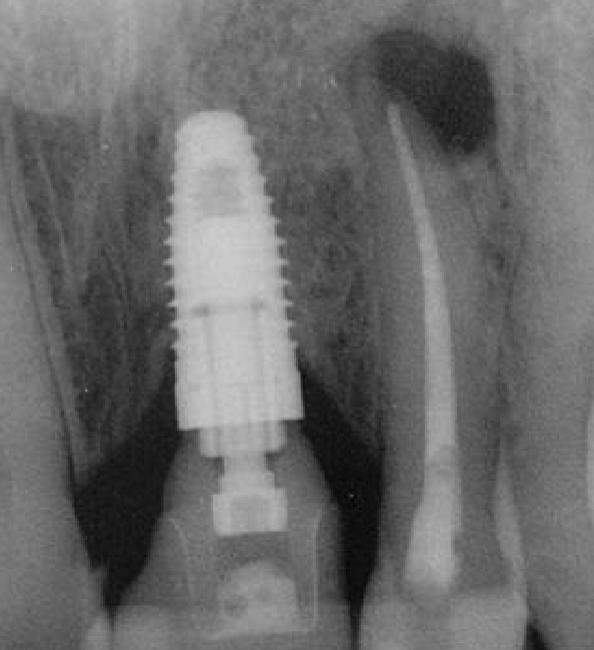

differentiate the pathology for #30 + #31

#30: apical rarefying osteitis

#31: developing tooth w/ open root apex

what’s the pathology of #7

apical rarefying osteitis

what’s the pathology of #30

apical sclerosing osteitis

describe the pathology

apical sclerosing osteitis + radiolucency around PDL space